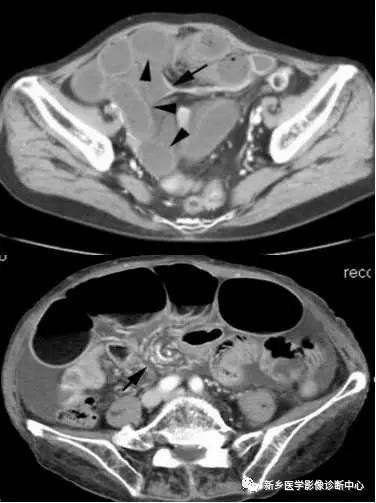

1.空肠不全性梗阻:空肠扩展呈弹簧状 。 2.空肠机械性梗阻:弹簧征

文章图片